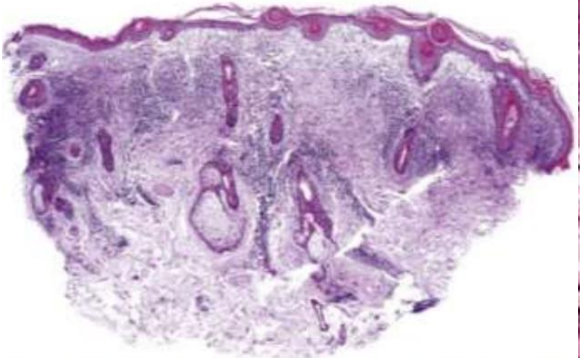

• 正角化和角化不全

• 只能 lymphocytes 浸潤 (狹義)

• 上皮和結締組織交界

• bandlike T cell

• Civatte body: 均質,退化的 keratinocyte

• basal cell hydropic degeneration

• saw-toothed Rete ridge